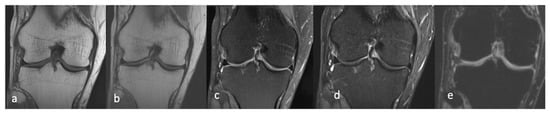

3.4. MRI

3.4.1. Morphological Sequences